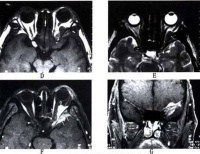

7.脑CT检查; CT诊断颅内肿瘤主要是根据肿瘤组织的密度改

颅内肿瘤

变和肿瘤对脑室系统的压迫移位来判断。有些肿瘤显示密度高,CT图像清晰;有的肿瘤因有钙化沉着,对比清楚;有些肿瘤或因瘤组织坏死,或因病灶周围水肿等变化而显示为均匀或不均匀之低密度区。颞叶肿瘤多为胶质瘤和脑膜瘤,CT检查多显示为高密度区,亦有少数肿瘤有钙化,囊变、坏死、水肿等显示其不同的密度变化。侧脑室和第三脑室常见受压、变形、移位等。